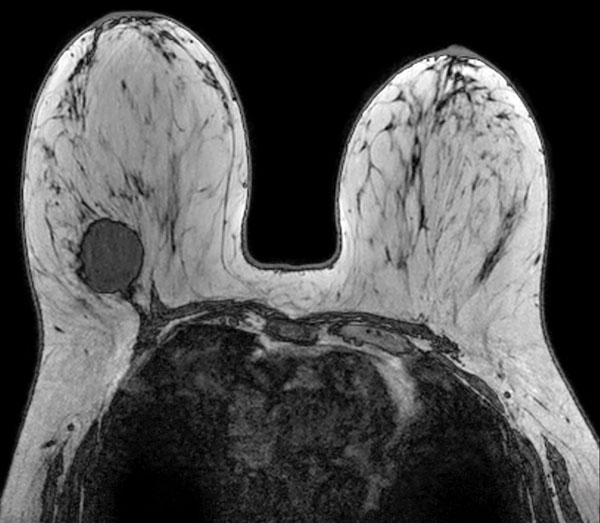

SmartBreast - dS Breast 7ch coil

Utrecht Medical Center, The Netherlands

Used Solution

• System

• Coil